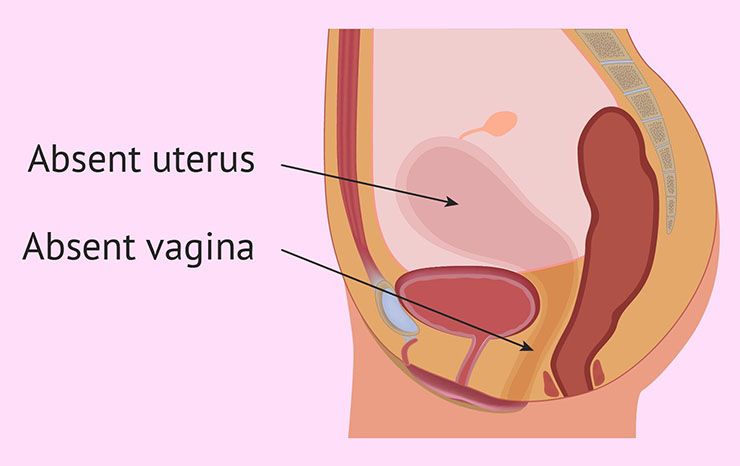

A Rare Condition

“Inspection of the vulva showed no vagina, only a shallow skin dimple was present below the external urethral meatus and between the labia minora,” authors wrote in a report about the rare case, which was published in the British Journal of Obstetrics and Gynecology.

An Impossible Pregnancy

According to the doctors on the case, the 15-year-old had been born with a birth defect called Mullerian agenesis or Mayer-Rokitansky-Kuster-Hauser syndrome. It meant that the girl had been born without a vagina. Despite this, doctors still believed she somehow had conceived a child.